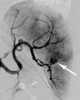

Intrasplenic hematoma

Splenomegaly